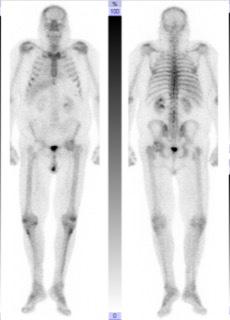

· PSMA-PET: Acetabulum-Met.

· Ossärer Progress (LWK 1)

· Metastasen: Femur & Oberarm

→ High-Volume mHSPC

Radiologisch: Komplette Remission ossärer Metastasen